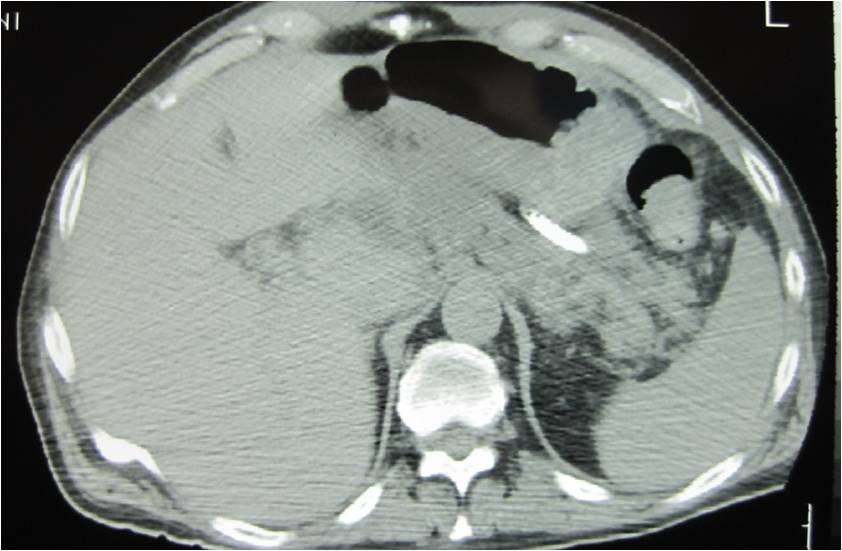

- Large abdominal abscess post- pancreatic surgery

- Successful drainage